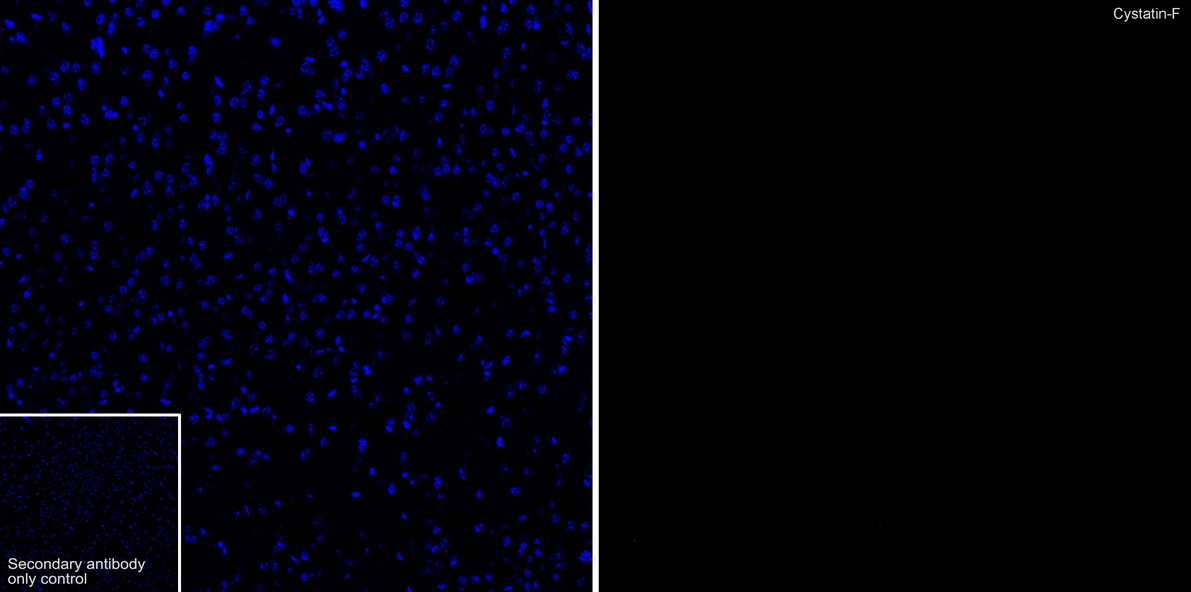

From www.huabio.com

Cystatin F Rabbit Monoclonal Antibody [PSH0900] (HA723053 Is Heat Bad For Bunnies If necessary, they can withstand temperatures up to 80 degrees, though they may be in some discomfort. If the temperature where your rabbit is, is above 77°f (25°c), it. At temperatures over 85 degrees, rabbits may show signs of overheating. Which is when they can develop heatstroke. Bunnies do not tolerate so much heat. You should also be cautious about. Is Heat Bad For Bunnies.

Cystatin F Rabbit Monoclonal Antibody [PSH0900] (HA723053 Is Heat Bad For Bunnies Rabbits aren’t able to tolerate heat well and can even die from being overheated. If the temperature where your rabbit is, is above 77°f (25°c), it. A temperature that’s above 25℃ (77℉) is too hot and equally dangerous for a rabbit. Generally speaking, you should factor in not just the temperature but also the humidity when designing your rabbit hutch. Is Heat Bad For Bunnies.